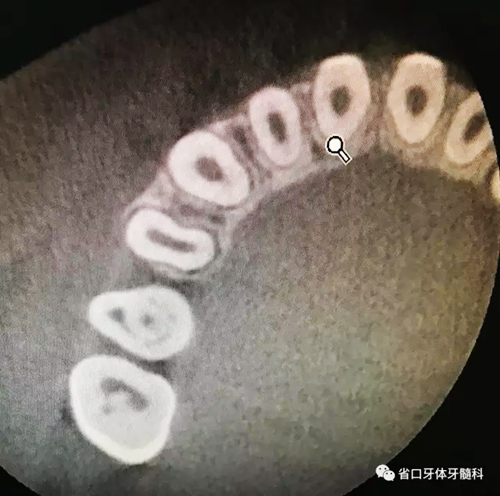

圖3 CBCT(2016-11-13):15由髓腔至根管內(nèi)見團塊阻射影像,阻射影中央為透射影,根尖1/3處見根管膨大,腭側(cè)牙槽骨破壞,根尖周低密度影范圍大,上頜竇黏膜增厚。